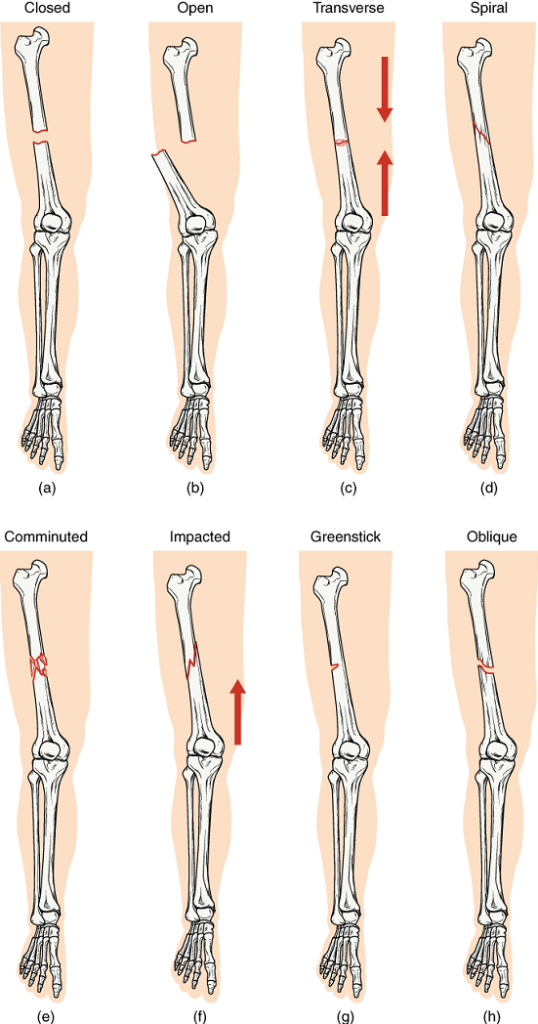

Types of Fractures: Fractures are classified by their complexity, location, and other features (Figure 16). Table 3 outlines common types of fractures. Some fractures may be described using more than one term because it may have the features of more than one type (e.g., an open transverse fracture). Of the types pictured in Figure 16 and Table 3, you are only required to understand the details of closed, open, comminuted, and greenstick fractures.

image

Figure 16. Types of Fractures. Compare healthy bone with different types of fractures:(a) closed fracture, (b) open fracture, (c) transverse fracture, (d) spiral fracture, (e) comminuted fracture, (f) impacted fracture, (g) greenstick fracture, and (h) oblique fracture.

Table 3: Types of Fractures

Type of fractureDescription

TransverseOccurs straight across the long axis of the bone

ObliqueOccurs at an angle that is not 90 degrees

SpiralBone segments are pulled apart as a result of a twisting motion

ComminutedSeveral breaks result in many small pieces between two large segments

ImpactedOne fragment is driven into the other (usually a result of compression)

GreenstickA partial fracture in which only one side of the bone is broken

Open (compound)A fracture in which at least one end of the broken bone tears through the skin; carries a high risk of infection

Closed (simple)A fracture in which the skin remains intact